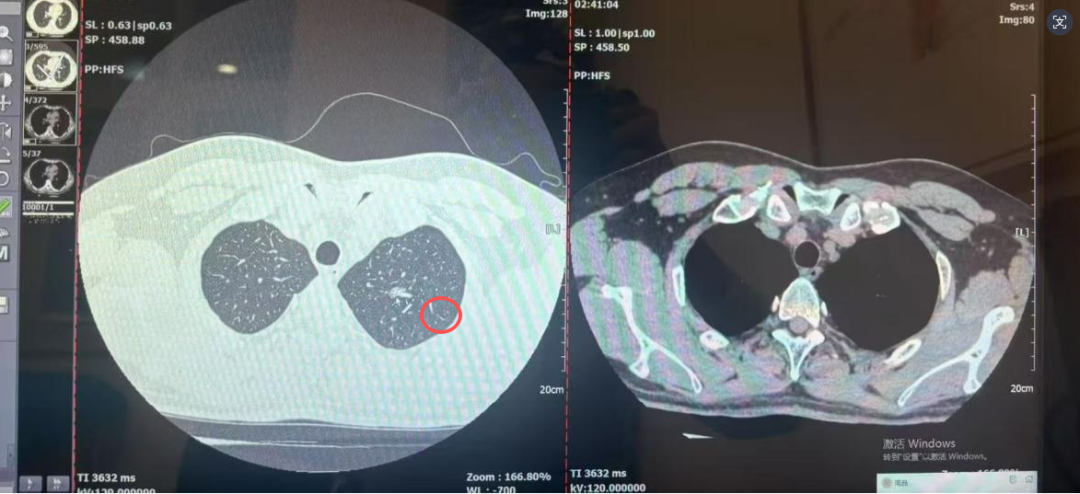

前段时间,刘先生不小心受凉感冒,咳嗽一直没好利索。想着排查下是不是合并了肺部感染,他便到西安医学院第一附属医院做了胸部 CT 检查。本以为只是常规检查,结果报告上的一句话让他瞬间慌了神:左肺上叶尖后段发现一个10mm×6mm的混合密度结节影。

“从你的症状看肺结节为感染性病变的可能不大,此次患病也与结节无关。考虑肿瘤病变可能。”呼吸与危重症医学科专家告诉刘先生;“你这结节是混合密度,形态上有恶性特征,大概率是早期肺癌,但不用怕,幸亏发现得早。”影像科专家指着CT影像说;心胸外科专家接着补充:“这个位置适合做胸腔镜微创手术,创伤小、恢复快”;病理科专家也耐心说明:“手术切除后我们会做病理检查,最终确认结节性质,为后续治疗提供准确依据”。